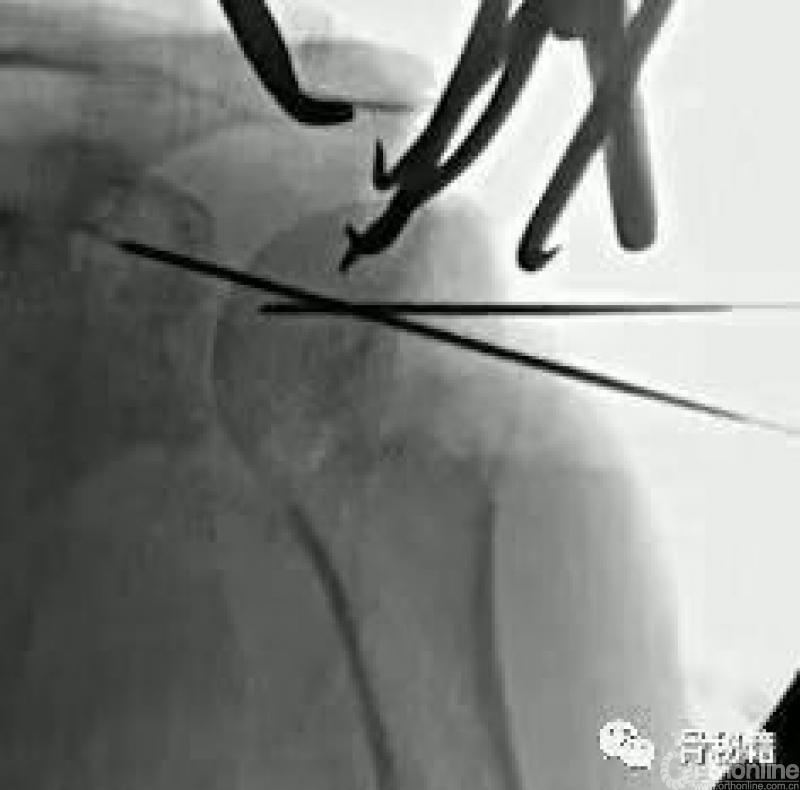

常用的克氏针的临时复位固定技术

可以应用大量的克氏针完成复位,

难复位的时候可以将头临时固定在关节盂上

最关键的就是剩余肱骨头需要进行外翻到合适的位置然后固定

将肱骨头的复位和合适的临时固定是最关键的

在复位好的基础上,植入合适的主钉导针

导针一旦植入,这个手术就完成了一半了